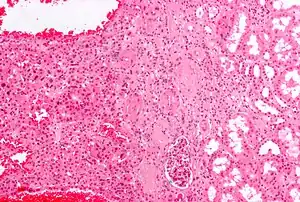

The salivary gland oncocytoma is a well-circumscribed, benign neoplastic growth also called an oxyphilic adenoma. It comprises about 1% of all salivary gland tumors. The histopathology is marked by sheets of large swollen polyhedral epithelial oncocytes, which are granular acidophilic parotid cells with centrally located nuclei. The granules are created by the mitochondria.